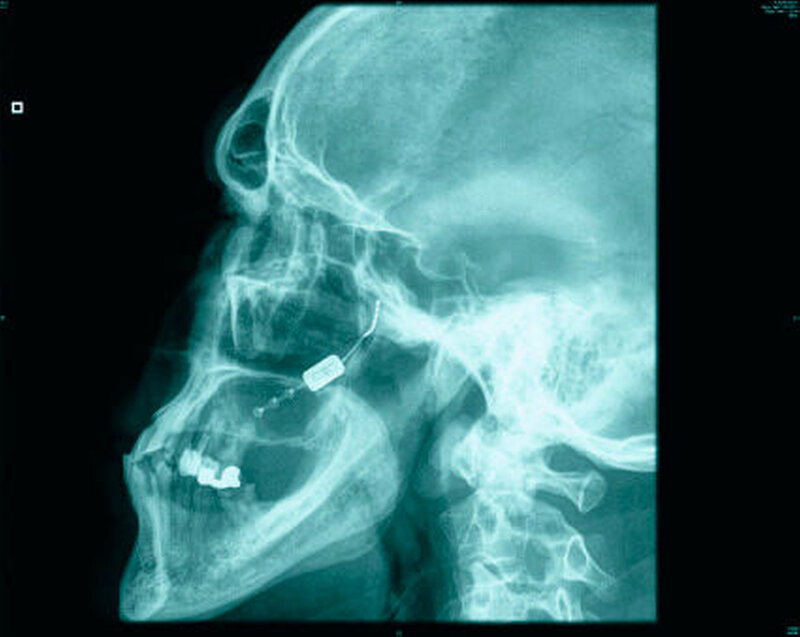

Ausschluss anderer Ursachen via Bildgebung

Diagnostisch wegweisend sind die Anamnese sowie die klinische Untersuchung. Eine Labordiagnostik sowie Bildgebung ist nicht primär zur Diagnosestellung, jedoch zum Ausschluss anderer Ursachen der Beschwerden wichtig.

Auszuschließen sind insbesondere ein Hirntumor, eine arteriovenöse Malformation, eine Karotisdissektion sowie ein Hirninfarkt und entzündliche Plaques. Im Rahmen der Erstdiagnostik werden daher in aller Regel eine kranielle Computertomografie, eine Kernspintomografie und gegebenenfalls auch eine Liquoruntersuchung veranlasst.

Bei ansonsten therapieresistenten Patienten mit chronischem Verlauf sind außerdem operative Verfahren zu erwägen. Ein Standardverfahren gibt es jedoch bislang nicht und ganz generell sind operative Eingriffe entsprechend der Leitlinien nur in „abso- luten Ausnahmefällen“ gerechtfertigt. Die Ursache hierfür liegt in der nicht unerheb- lichen Gefahr, durch die Maßnahmen eine zusätzliche und dann iatrogen verursachte Neuralgie des Nervus trigeminus oder eine Anaesthesia dolorosa hervorzurufen.

Als neues vielversprechendes Verfahren nennt die DMKG aber die elektrische Stimulation des großen Hinterhauptnervs. Erprobt wird auch die Tiefenhirnstimulation des Hypothalamus. Bei beiden Verfahren gibt es Belege für eine initiale Besserung, allerdings wurde jeweils auch eine sekundäre Verschlechterung gesehen. Entsprechend den Angaben in den Leitlinien gibt es nach derzeitiger Kenntnis eine 50-prozentige Chance, mittels solcher Verfahren eine Besserung der Klinik zu erwirken.